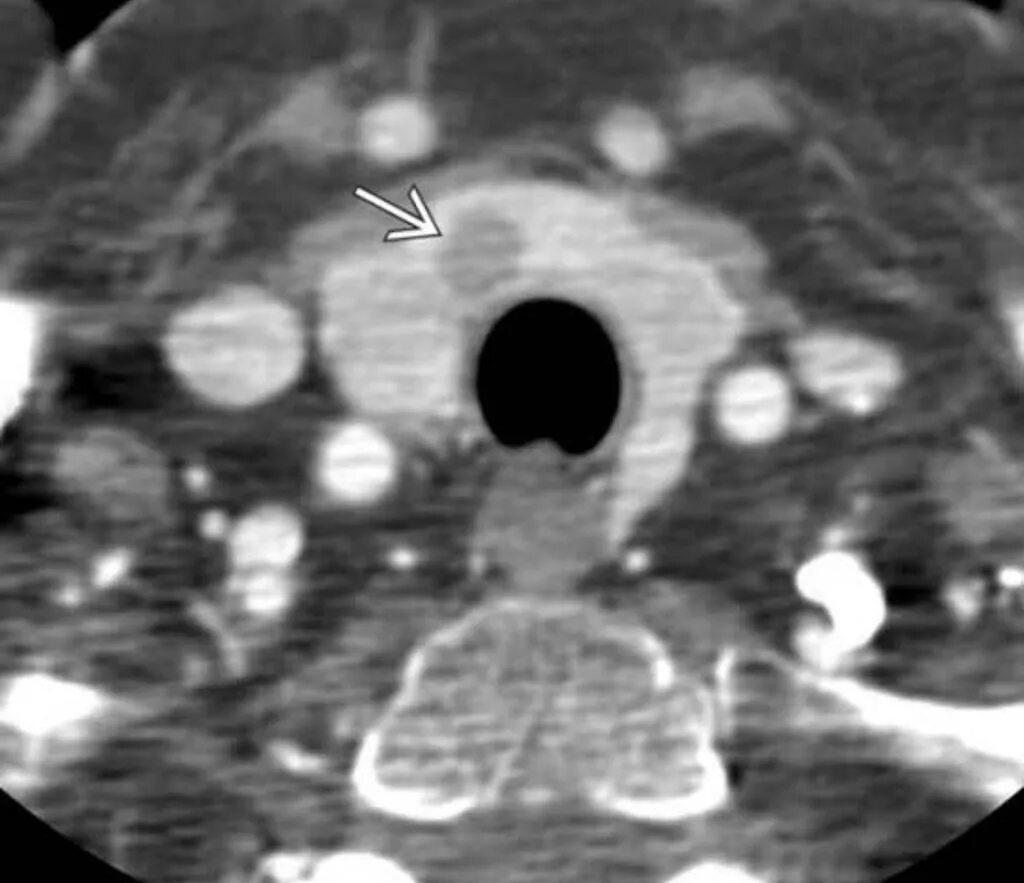

Золлингера эллисона синдром симптомы у взрослых